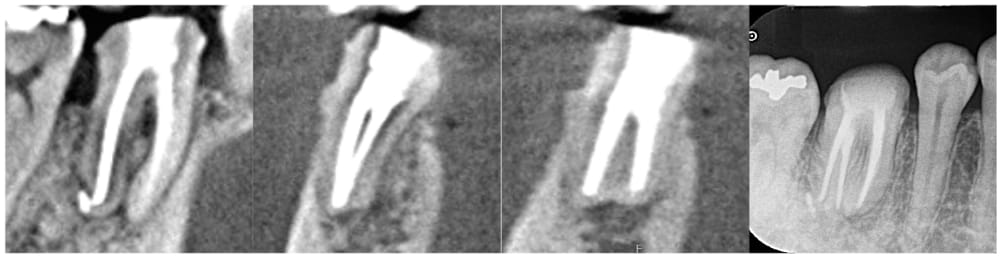

6ヶ月後の経過観察時には初診時の噛んだ時の鈍痛は消失していました。レントゲン、CTにて、根尖部の明瞭な骨の回復が認められ、治療がうまく奏功していることが確認できました。

通常であれば術後12ヶ月まで経過をみますが、骨も完全に回復していること、症状がないことから、かかりつけ歯科医院にて最終補綴(かぶせもの)を行ってもらうことになりました。

通常、根尖部の骨吸収の回復には1年程度かかると言われていますが、症例によっては今回のように半年程度ではっきりと改善が認められる場合もあります。一方で、術後1年では全く変化がなく、2年3年と経過するにともない徐々にゆっくりと改善する場合もあります。どの程度のスピードで回復するかは術前には予想が難しく、今回は偶然ですがうまくスピーディーに治癒した事例であるといえます。